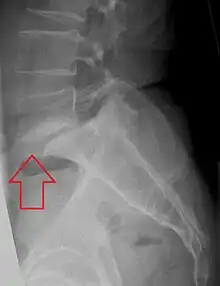

| X-ray of the lateral lumbar spine with a grade III anterolisthesis at the L5-S1 level | |

Spondylolisthesis is when one spinal vertebra slips out of place compared to another.[1] While some medical dictionaries define spondylolisthesis specifically as the forward or anterior displacement of a vertebra over the vertebra inferior to it (or the sacrum),[2][3] it is often defined in medical textbooks as displacement in any direction.[4][5]

Spondylolisthesis is graded based upon the degree of slippage of one vertebral body relative to the subsequent adjacent vertebral body.[6] Spondylolisthesis is classified as one of the six major etiologies: degenerative, traumatic, dysplastic, isthmic, pathologic, or post-surgical.[7] Spondylolisthesis most commonly occurs in the lumbar spine, primarily at the L5-S1 level, with the L5 vertebral body anteriorly translating over the S1 vertebral body.[7]